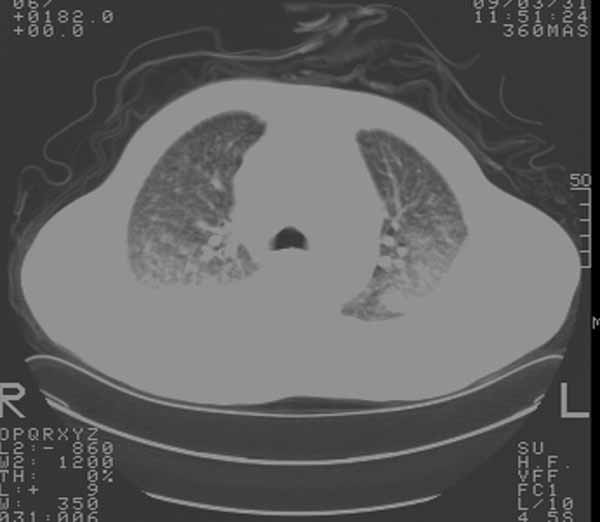

以下是引用余辉在2009-3-31 18:43:00的发言:[br]肺水肿,双侧心腔积液,心包积液,心影增大,疑似心衰

以下是引用wangyong1977在2009-3-31 20:46:00的发言:[br]肺水肿,双侧胸腔积液,心包积液,心影增大,疑似心衰 [br]

以下是引用宇宙ct在2009-3-31 18:57:00的发言:[br]肺水肿,双侧心腔积液,心包积液,心影增大,疑似心衰 [br] [br]